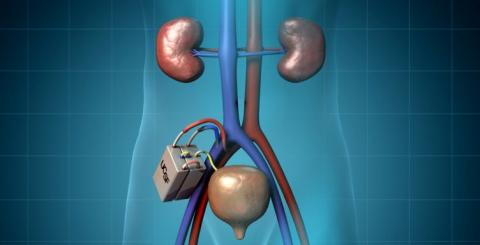

신장이 안 좋으면 몸 속 노폐물, 불순물 등이 걸러지지 않기 때문에 각양각색 문제가 발생해요. 특히, 하루종일 감당하기가 힘들만큼 피곤하며, 기력이 없는 증상을 느끼게 됩니다. 이렇게 피곤하고 신장이 안좋으면 나타나는 증상입니다. 따라서 신장기능이 망가져 버린 만성 신장질환자들은 혈액 투석기를 통해 피의 노폐물을 제거하여 여러가지 증상들을 미리 막는게 좋겠습니다.